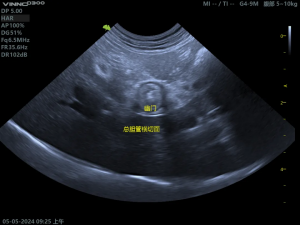

(2)胆囊粘液囊肿影像

胆囊内呈现“猕猴桃征”或“星芒状”的回声。胆囊壁增厚、胆泥淤积、可评估胆囊是否破裂。

胆总管冲洗:同时探查并冲洗总胆管,确保其通畅。